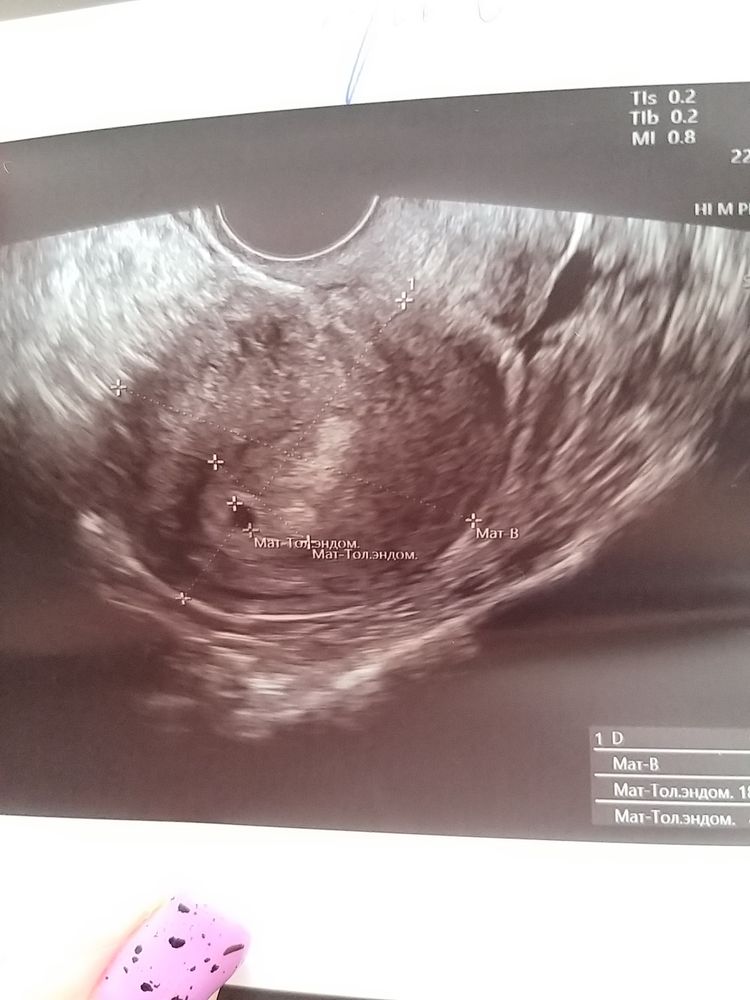

вот моё первое, 5 недель эмбриональных и 6 поставили по узи, плодное яйцо 21 мм, ктр 6.9 мм и собственно плод уже видно